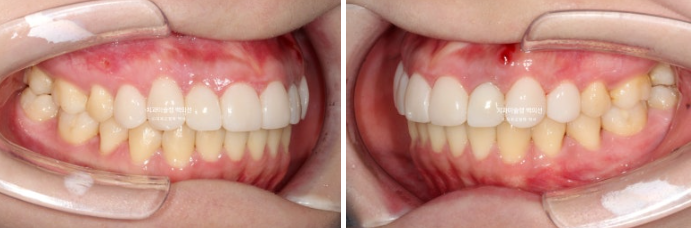

10개월간 안모 변화 보겠습니다.

23.12~24.10

거미스마일은 개선되었고 하관이 벌써 짧아진 것이 보입니다.

거미스마일과 돌출, 특히 잇몸이 튀어나온 잇몸돌출은 많이 좋아졌습니다.

앞니가 뒤로 들어가며 호두주름이 사라졌습니다.

입이 처음보다 편하게 다물립니다.

안모의 확실한 개선을 확인 한 후 환자분과 상의 하에 중심선 개선 및 교합 개선을 위해 추가장치 제작에 들어갔습니다